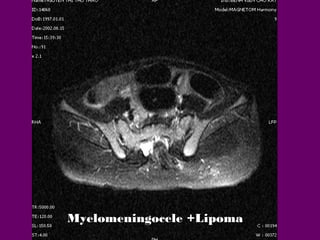

Myelomeningocele

Myelomeningocele +Lipoma